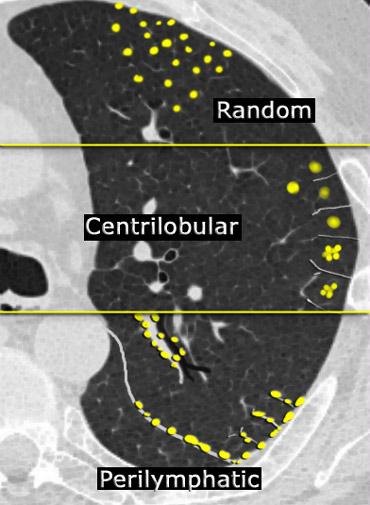

Phân bố dạng nốt trên HRCT

Sự phân bố của các nốt quan sát được trên HRCT là yếu tố quan trọng nhất để đạt được chẩn đoán chính xác trong dạng nốt.

Trong hầu hết các trường hợp, các nốt nhỏ có thể được phân loại theo một trong ba kiểu phân bố: quanh bạch mạch, trung tâm tiểu thùy, hoặc ngẫu nhiên. Phân bố ngẫu nhiên đề cập đến các nốt không có xu hướng ưu tiên vị trí cụ thể nào trong tiểu thùy phổi thứ cấp.

Sự phân bố của các nốt trên HRCT là yếu tố quan trọng nhất trong việc đưa ra chẩn đoán chính xác theo dạng nốt:

- Phân bố quanh bạch mạch bao gồm các nốt nằm liên quan đến bề mặt màng phổi, vách gian tiểu thùy và mô kẽ quanh phế quản-mạch máu. Các nốt này hầu như luôn luôn có thể nhìn thấy ở vị trí dưới màng phổi, đặc biệt là tiếp giáp với các khe liên thùy.

- Phân bố trung tâm tiểu thùy được đặc trưng bởi các nốt khu trú ở vùng trung tâm tiểu thùy. Khác với các nốt quanh bạch mạch và ngẫu nhiên, các nốt trung tâm tiểu thùy không liên quan đến bề mặt màng phổi. Các nốt ngoại vi nhất thường có tâm cách khe liên thùy hoặc bề mặt màng phổi 5–10 mm.

- Phân bố ngẫu nhiên. Các nốt phân bố ngẫu nhiên được phân tán không có xu hướng ưu tiên so với các cấu trúc phổi hoặc tiểu thùy thứ cấp.

Mặc dù chúng có thể liên quan đến bề mặt màng phổi và khe liên thùy, nhưng chúng không có sự ưu thế dưới màng phổi như thường thấy trong phân bố quanh bạch mạch.